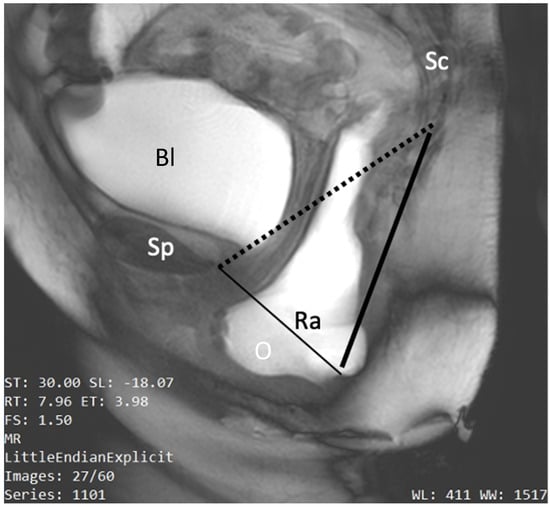

5.2.5. The Pubococcygeal Line (PCL)

5.2.6. The HMO Classification System

- Pelvic organ descent: defined as the difference between the resting and straining positions of the bladder neck, prostate base, vaginal vault, and anorectal junction (ARJ). This descent is measured relative to a reference line (PCL or horizontal line) and indicated by a number preceded by a minus sign (−) for above or a plus sign (+) for below the reference. Normal values are −3 cm for the bladder base, prostate, and vaginal vault and −2 cm for the ARJ.